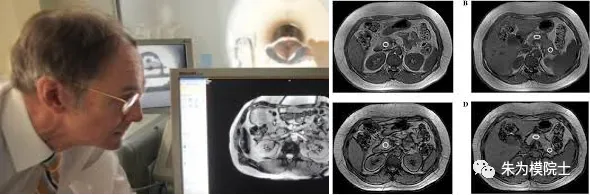

泰勒教授在研究如何测定胰腺里的脂肪多少